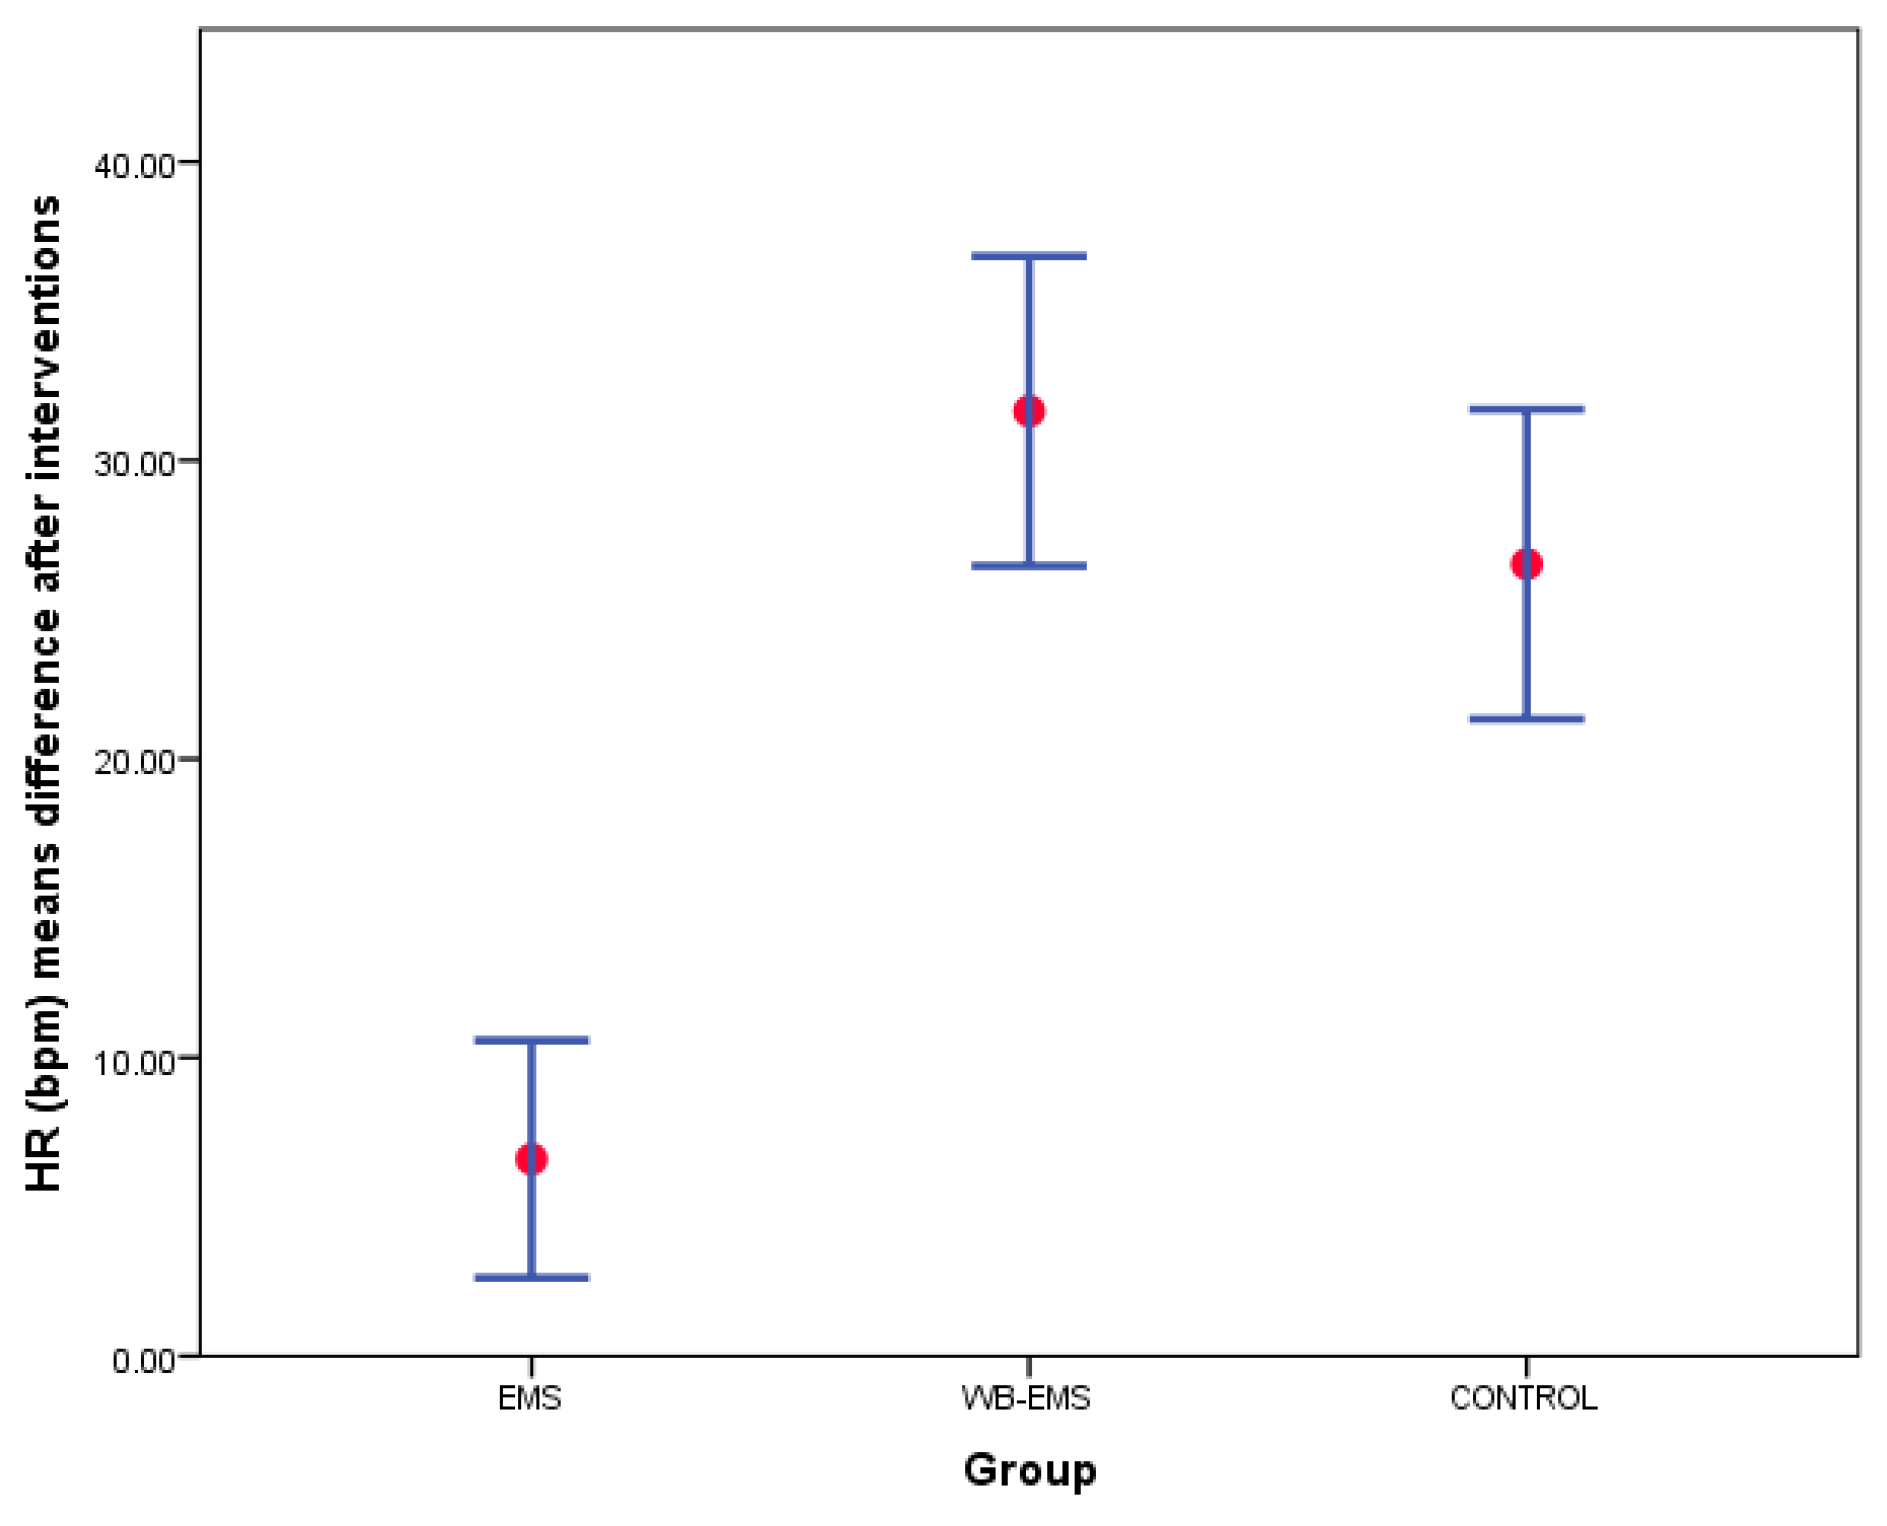

3.3. Outcome Measurements Differences after Interventions

3.4. Two-Way ANOVA of Repeated Measurements for Intra- and Intergroup Comparisons

| HR (bpm) | 78.40 ± 15.49 (51–118) | 85.00 ± 22.28 (53–137) | 6.60 ± 12.42 (−22–31) | 73.47 ± 13.16 (51–100) | 105.12 ± 18.12 (59–137) | 31.65 ± 16.22 (1–71) | 74.10 ± 15.68 (54–116) | 100.62 ± 20.81 (59–137) | 26.52 ± 16.22 (−4–75) | <0.001 * |